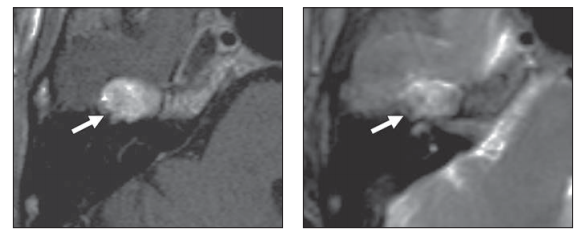

图5,多发性硬化

患者,左:FLAIR;右:T1增强,面神经迷路段异常增强,膝状神经节正常增强

图6,T1增强,慢性炎性脱髓鞘多神经病患者右侧迷路段、膝状神经节异常增强,可以看到右侧膝状神经节信号较左侧明显